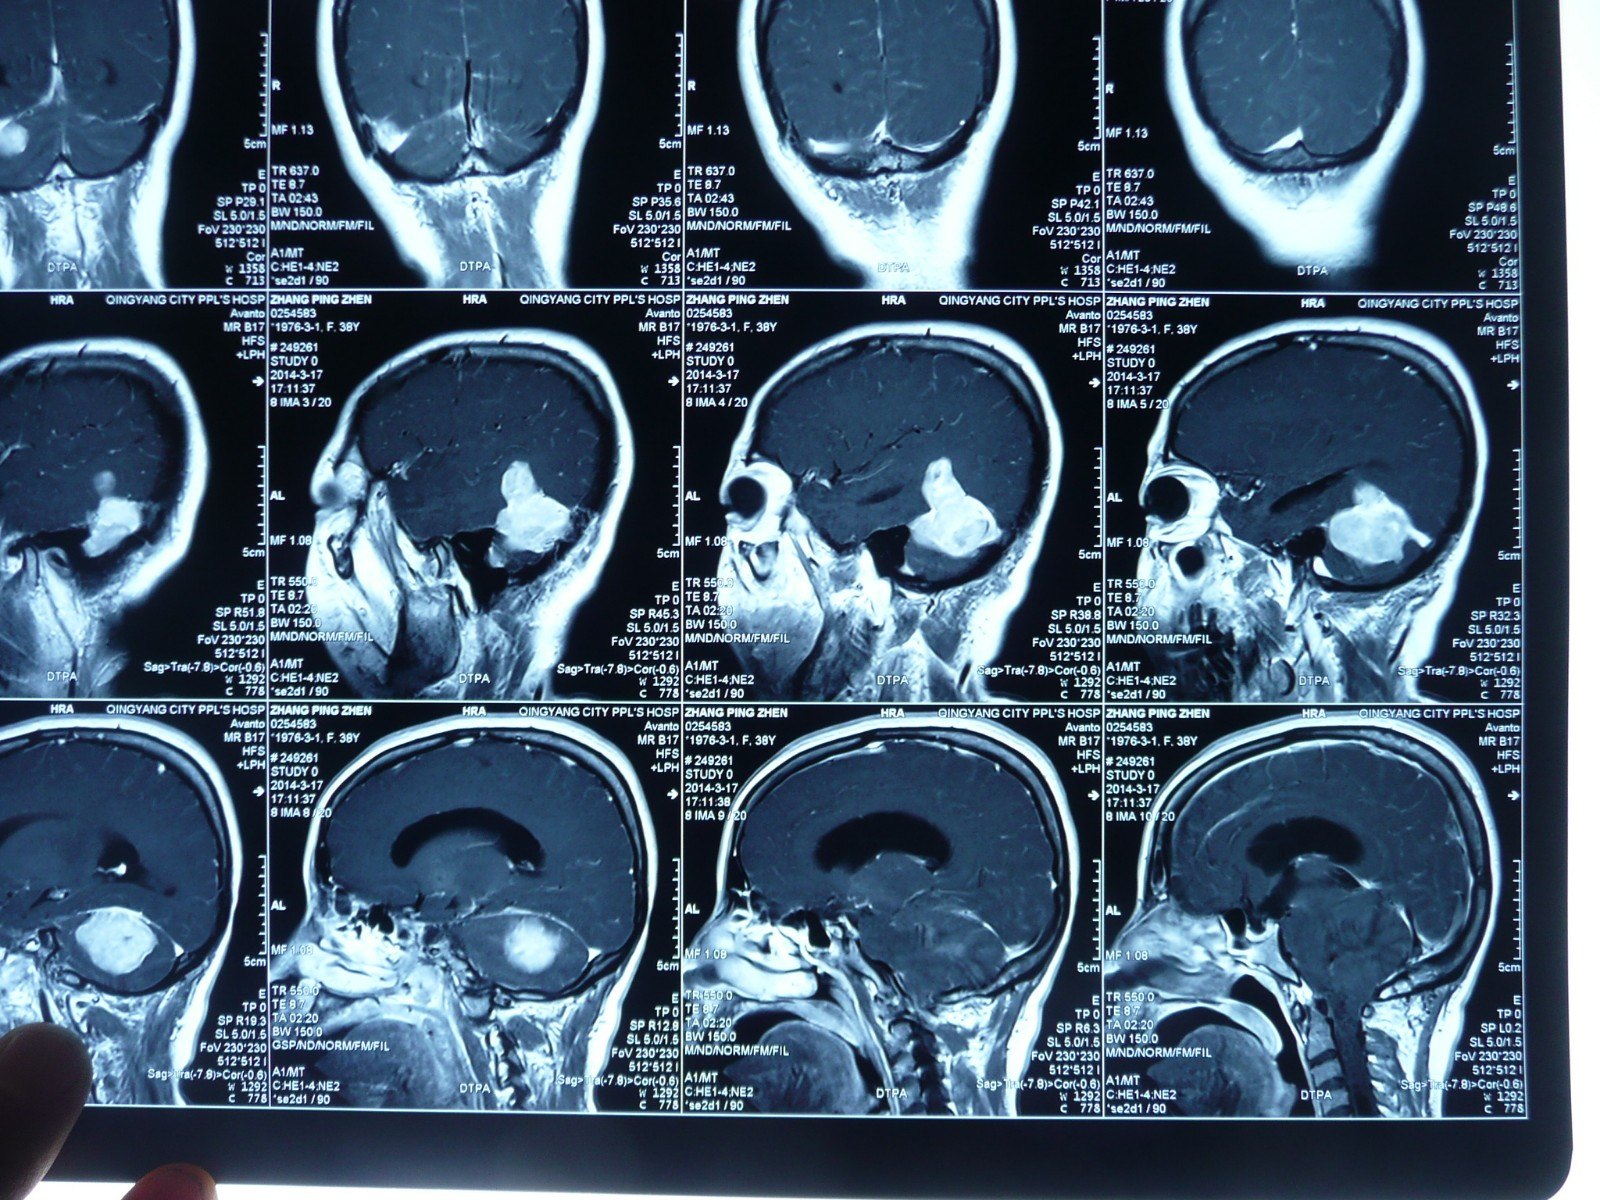

贺晓生教授小脑幕上下骑跨脑膜瘤的外科切除手术案例 - 好大夫在线

原创贺晓生教授小脑幕上下骑跨脑膜瘤的外科切除手术案例

左小脑占位,是否有明显尾征,能确定小脑幕脑膜瘤么